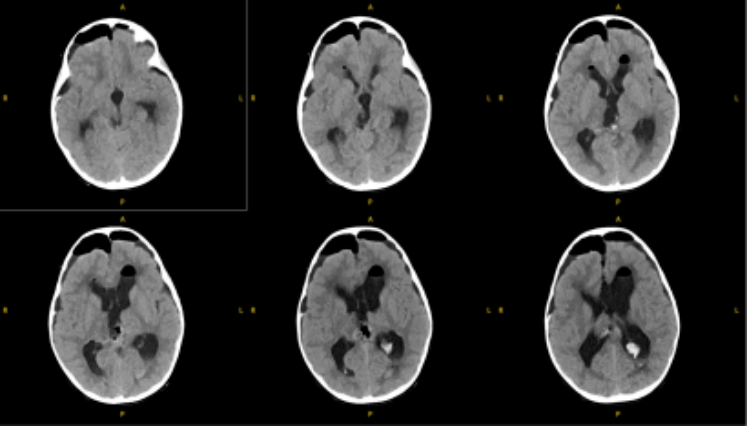

患儿术后MRI图像

术后病理考虑为颅内间叶源性肿瘤,非脑膜上皮来源。FISH提示EWSR1不典型断裂阳性。术后MRI显示肿瘤完全切除。目前患儿情况稳定,由ICU转入普通病房。

患儿术后MR影像:松果体区肿瘤组织切除完全